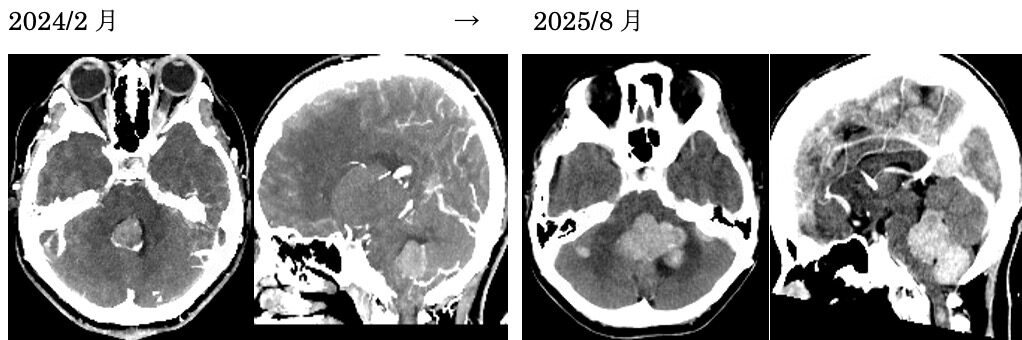

NF2による多発脳腫瘍の患者さんで、福島孝徳先生から引き継いで診ている患者さん。前回右前頭部の腫瘍を手術しましたが、その他の腫瘍も徐々に増大してきました。今回は第四脳室内腫瘍を摘出しました。腫瘍の一部が脳室底と癒着しており、わずかにこの部を残存させましたが、ちょうど顔面神経丘のところであったため術後左顔面まひ、外転神経麻痺が出現しました。顔面麻痺は数日で治癒し、外転神経麻痺も眼位はすぐに元に戻りましたが、自覚的な複視は残存しています。